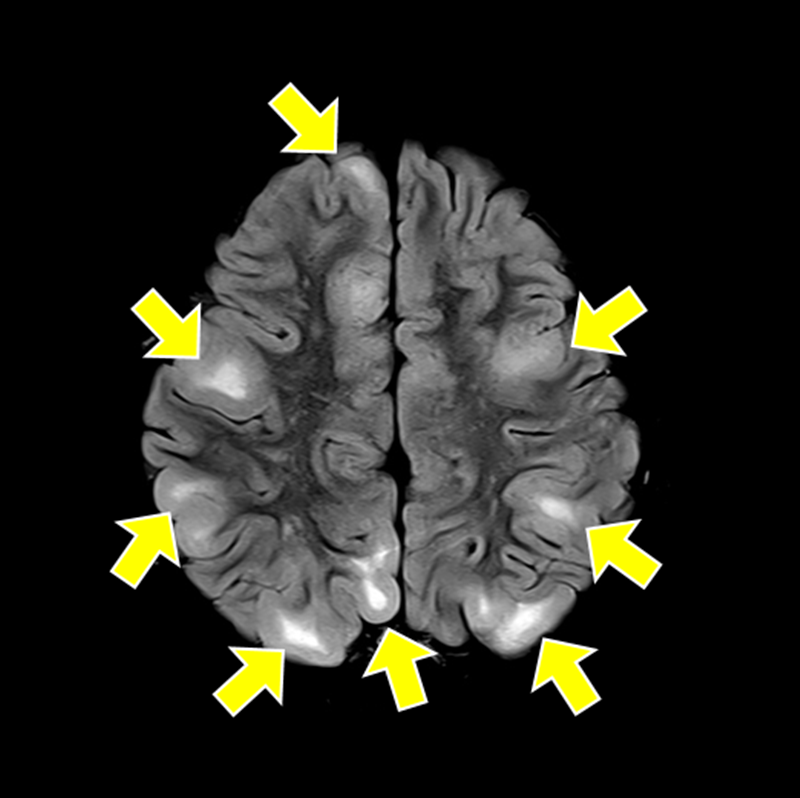

▲ A brain MRI scan of a patient with tuberous sclerosis complex, in which benign tumors develop in multiple organs, showing multiple cortical tubers (TSC) (indicated by yellow arrows).